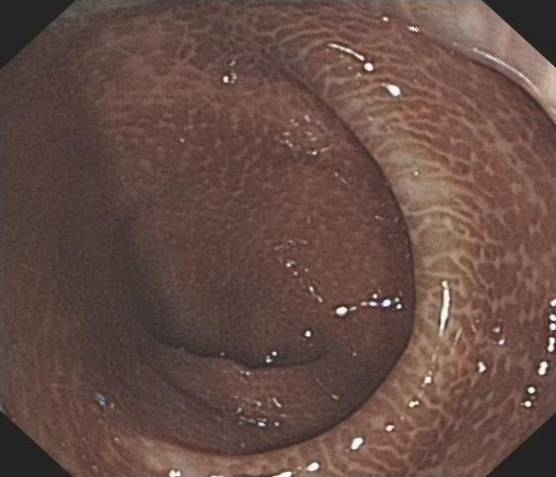

▲ 正常人的结肠VS 黑变病结肠

医生给小蔡做了肠镜,没想到,肠壁上到处都是星星点点的黑斑,就是肠粘膜反复受损所致。而更不幸的是,医生发现了其中一块黑斑竟已癌变。